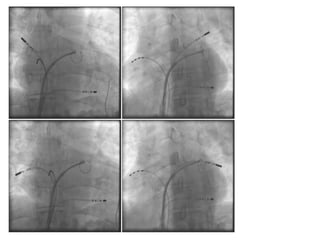

2. Mapeo / Ablación

Ablación en RS  Aislamiento VVPP

Aislamiento VPSI